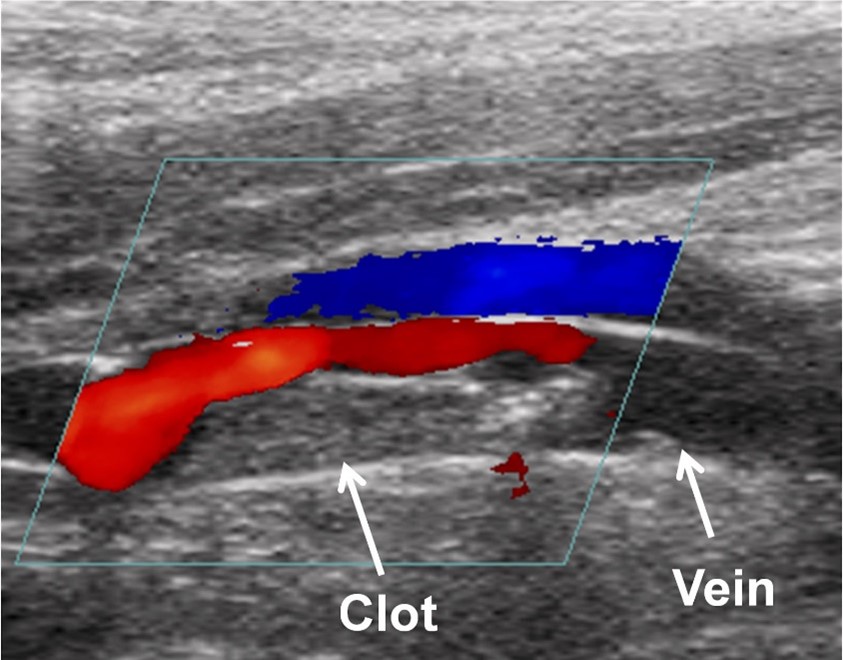

Các nghiên cứu siêu âm hai mặt nên được thực hiện để xác định chẩn đoán huyết khối tĩnh mạch sâu (DVT) và xác định vị trí của cục máu đông. Nghiên cứu này được thực hiện bằng cách đặt một đầu dò bên ngoài lên da ở (các) vùng nghi ngờ có huyết khối tĩnh mạch sâu (DVT). Các tĩnh mạch được hình dung bằng sóng âm thanh đi qua các mô của chi.